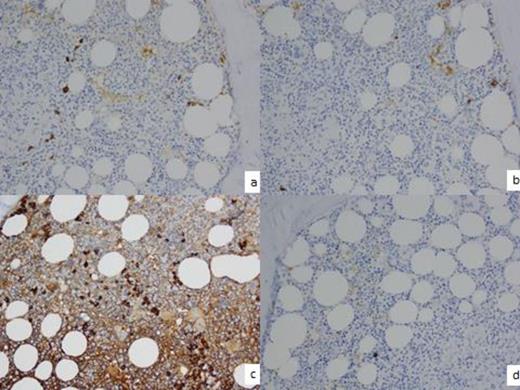

Few PCs + kappa light chain by IHC. 3b. Few PCs + for lambda light chain by IHC 3c. Majority of PCs show + IgG by IHC. 3d. PCs - IgM by IHC.